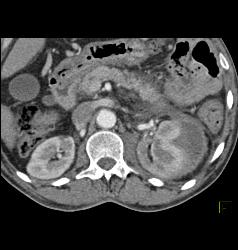

Iliac Artery Aneurysm With Iliopsoas Bleed